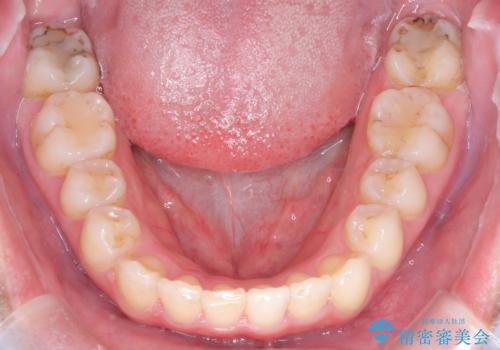

矯正後の後戻り インビザラインで改善

- 前歯のガタツキが気になると来院されました。

マウスピース矯正治療を選択しました。

前歯のガタツキを改善する治療法として、マウスピース矯正が適していることが多いです。

マウスピース矯正は、金属製のブラケットやワイヤーを使用せずに、透明なマウスピースを装着して歯を移動させる方法です。そのため、目立たず、痛みも少ないです。